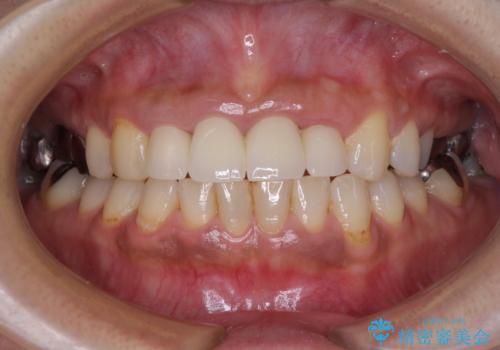

汚れた仮歯が気になる 前歯のオールセラミッククラウン

- 地元の歯科医院にて前歯4歯を仮歯に替えたものの、汚れていることが気になるとのことで来院された患者様です。

不適な仮歯の影響で歯肉が腫れていたため、新しい仮歯に替えた後に歯肉の腫れが引くのを待ち、オールセラミッククラウンにて補綴することとしました。

仮歯を変えたことで歯肉の腫れは引き、根管治療も功を奏して膿の出口はきれいに消退しました。